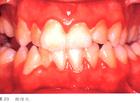

牙髓炎: 牙髓炎是指细菌或毒素侵入位于牙齿中心的牙髓引起的炎症。以自发性、阵发性疼痛为主症。临床常分为可复性牙髓炎、不可复性牙髓炎、牙髓变性和牙髓坏死。多采用除去牙髓的方法治疗。绝大多数根尖周的病变,特别是炎症,都是继发于牙髓病的。根尖周病变时,也可影响牙髓。 急性牙髓炎是指急性牙髓组织的炎症,其感染源主要来自深髓,牙髓的感染可通过根尖孔引起根尖感染,临床主要特征是剧烈疼痛,一般止痛药物效果不明显,后期可发展为牙髓坏疽,治疗主要有开髓及药物止痛。

牙髓炎